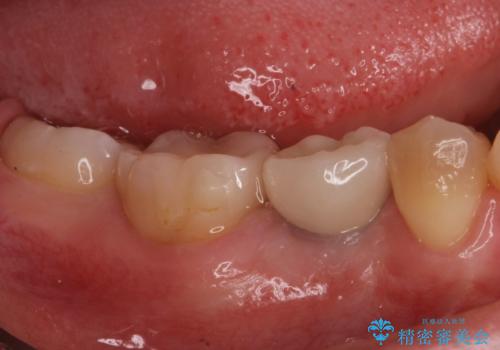

併用して銀歯も気になるとの事でしたのでセラミック治療も行いました。

適合の良いセラミックが入りました。